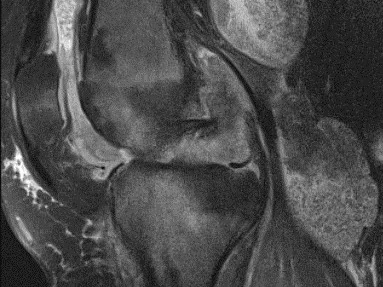

This online rheumatology course will help learners gain knowledge of basic and advanced imaging of rheumatologic conditions including- osteoarthritis, erosive OA, rheumatoid arthritis, CPPD arthropathy, Ca HADD, SLE, psoariasis, reactive arthritis, scleroderma, Gout, and axial spondyloarthritis, etc. The imaging modalities will include radiographs, US, DECT, and MRI.